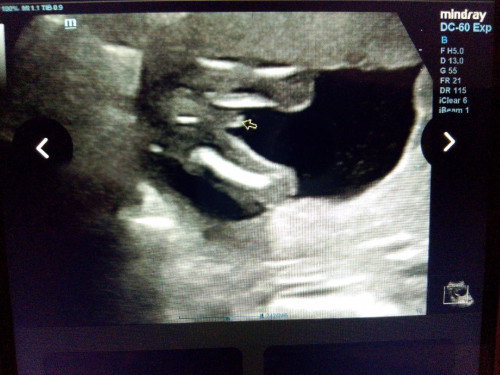

Saya cirit birit dari awal mengandung sampai sekarang tapi ada masa najis okay ada masa cair. Sehari tu paling banyak pun 3 kali tapi bukan setiap hari. Normally sekali je cirit. Saya memang susah minum air. Makan pun sikit. Sejak kena gastrik teruk masa awal hanil tu saya jadi kurang nak makan. Makan lebih je bloated. Saya pula nak demand2 suami pun suami baru dapat keje yang gaji kena downgrade disebabkan komitmen tinggi saya makan je apa ada. Result urine pagi mild anemia je. Plus now saya baru nak tukar pada iberet punya vitamin. Supposedly harini dapat multivitamin and ors tapi maybe doc lupa bagi. And.. sebabkan cirit lama lebih sebulan, doc suruh ambil sample darah and najis utk check further. Ada tak yg pengalaman macam saya? Saya takut nak warded :'( #Needadvice #ciritbirit #trimester1 #mohonbantujawabbunda #11weeks